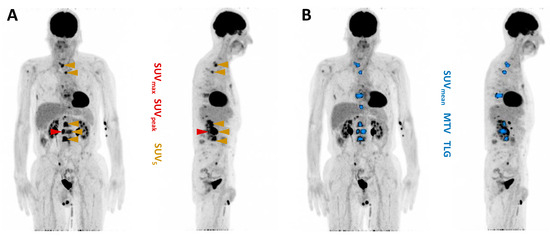

2.4. Evaluation of Predictive Biomarkers

| MTV | Metabolic tumor volume |

| SUV | Standardized uptake value |

| SUVmax | Maximum standardized uptake value |

| SUVpeak | Peak standardized uptake value |

| SUVmean | Mean standardized uptake value |

| TLG | Total lesion glycolysis |